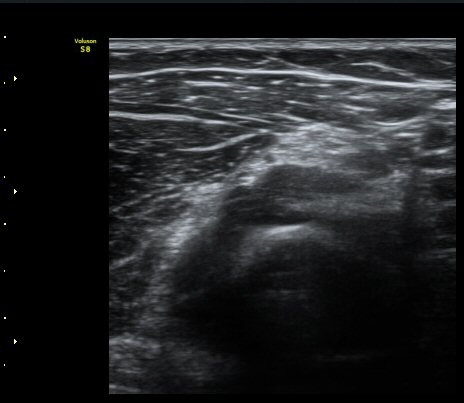

[ÆÈ²ÞÄ¡] Å״Ͻº¿¤º¸¿ì(¿Ü»ó°ú¿°)¿¡ µ¿¹ÝµÈ ¿ä°ñ½Å°æ Èİñ°£ºÐÁö º´Áõ 2

ÃÊÀ½ÆÄ °Ë»ç